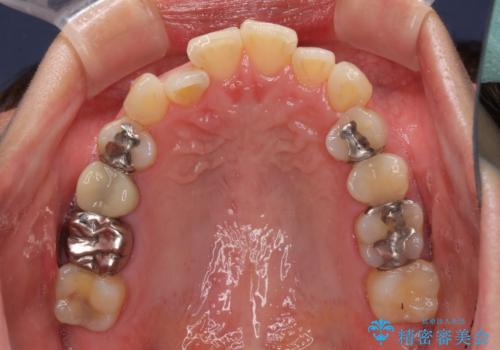

切端咬合をインビザライン矯正で解消

- 前歯のデコボコを気にして来院された患者様です。

上下前歯の先端同士が接触する切端咬合であったため、上顎は歯列を拡大し、下顎はIPR(歯と歯の間を削る)により叢生を解消しながら歯列を小さくすることとしました。

治療途中に前歯に歯髄充血を思わせる痛みが認められたため、無理のない歯の移動と頻繁な経過観察を行いました。

切端咬合はスムーズに解消され、前歯の負担を軽減させることができました。